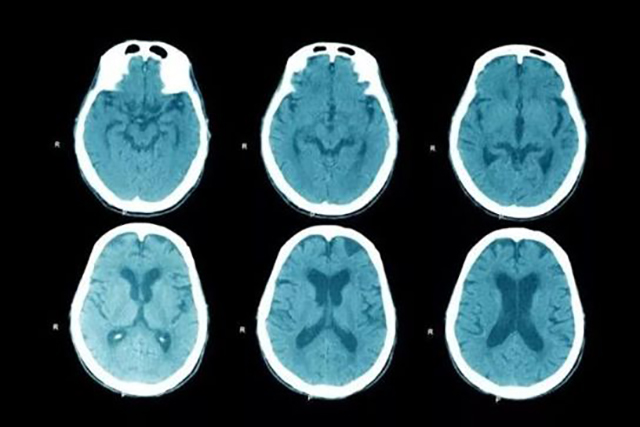

正念不但对ADHD或ADD有改善作用,对于有压抑或焦虑的人群也有很好的缓解作用,最常见的是用于辅助焦虑症、失眠障碍、注意力缺失方面的辅助治疗。已有诸多功能脑成像扫描证实。

△ fMRI扫描对比正念减压对大脑的影响

图中上排为对有焦虑抑郁倾向人的大脑扫描;下排对应的经过12周正念减压强化训练后的扫描,图中能明显看到大脑中神经元链接的激活状态变化(基于非创伤的脑神经含氧水平成像,面积大代表神经链接强化)